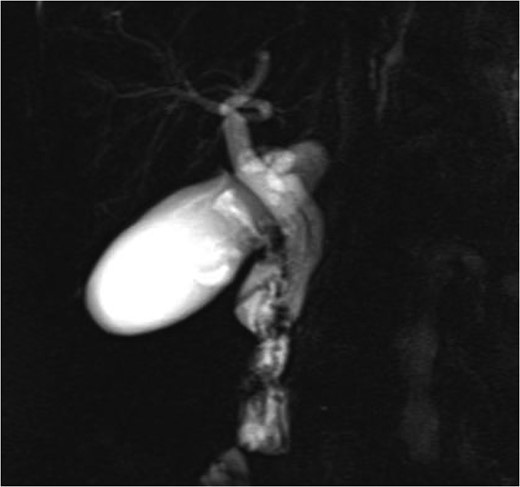

While ultrasound and CT are able to detect dilated cystic ducts, normal cystic ducts with diameters in the range of 1–5 mm are often not detected with these modalities. MRCP is an accurate imaging modality in detecting aberrant ductal anatomy, demonstrating a cystic duct in 74% of patients [5]. Direct cholangiography, including ERCP and intraoperative cholangiography, is invasive but readily identifies anatomical variations. In this case, MRCP correctly identified the course and insertion of the cystic duct relative to the common hepatic duct (Fig. 1).

MRCP image showing long parallel course of the cystic duct inserting medially just proximal to the ampulla of Vater.